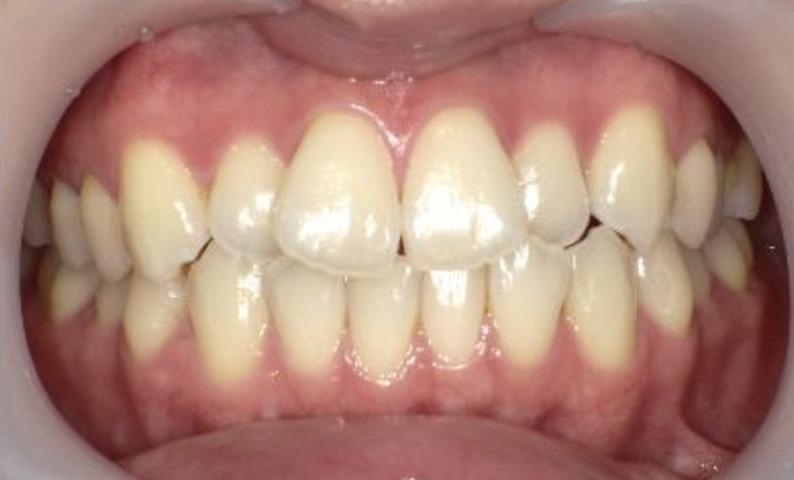

症例_025 上下顎の部分矯正

治療期間:13ヶ月金額:51万円+税女性前歯のガタガタ出っ歯